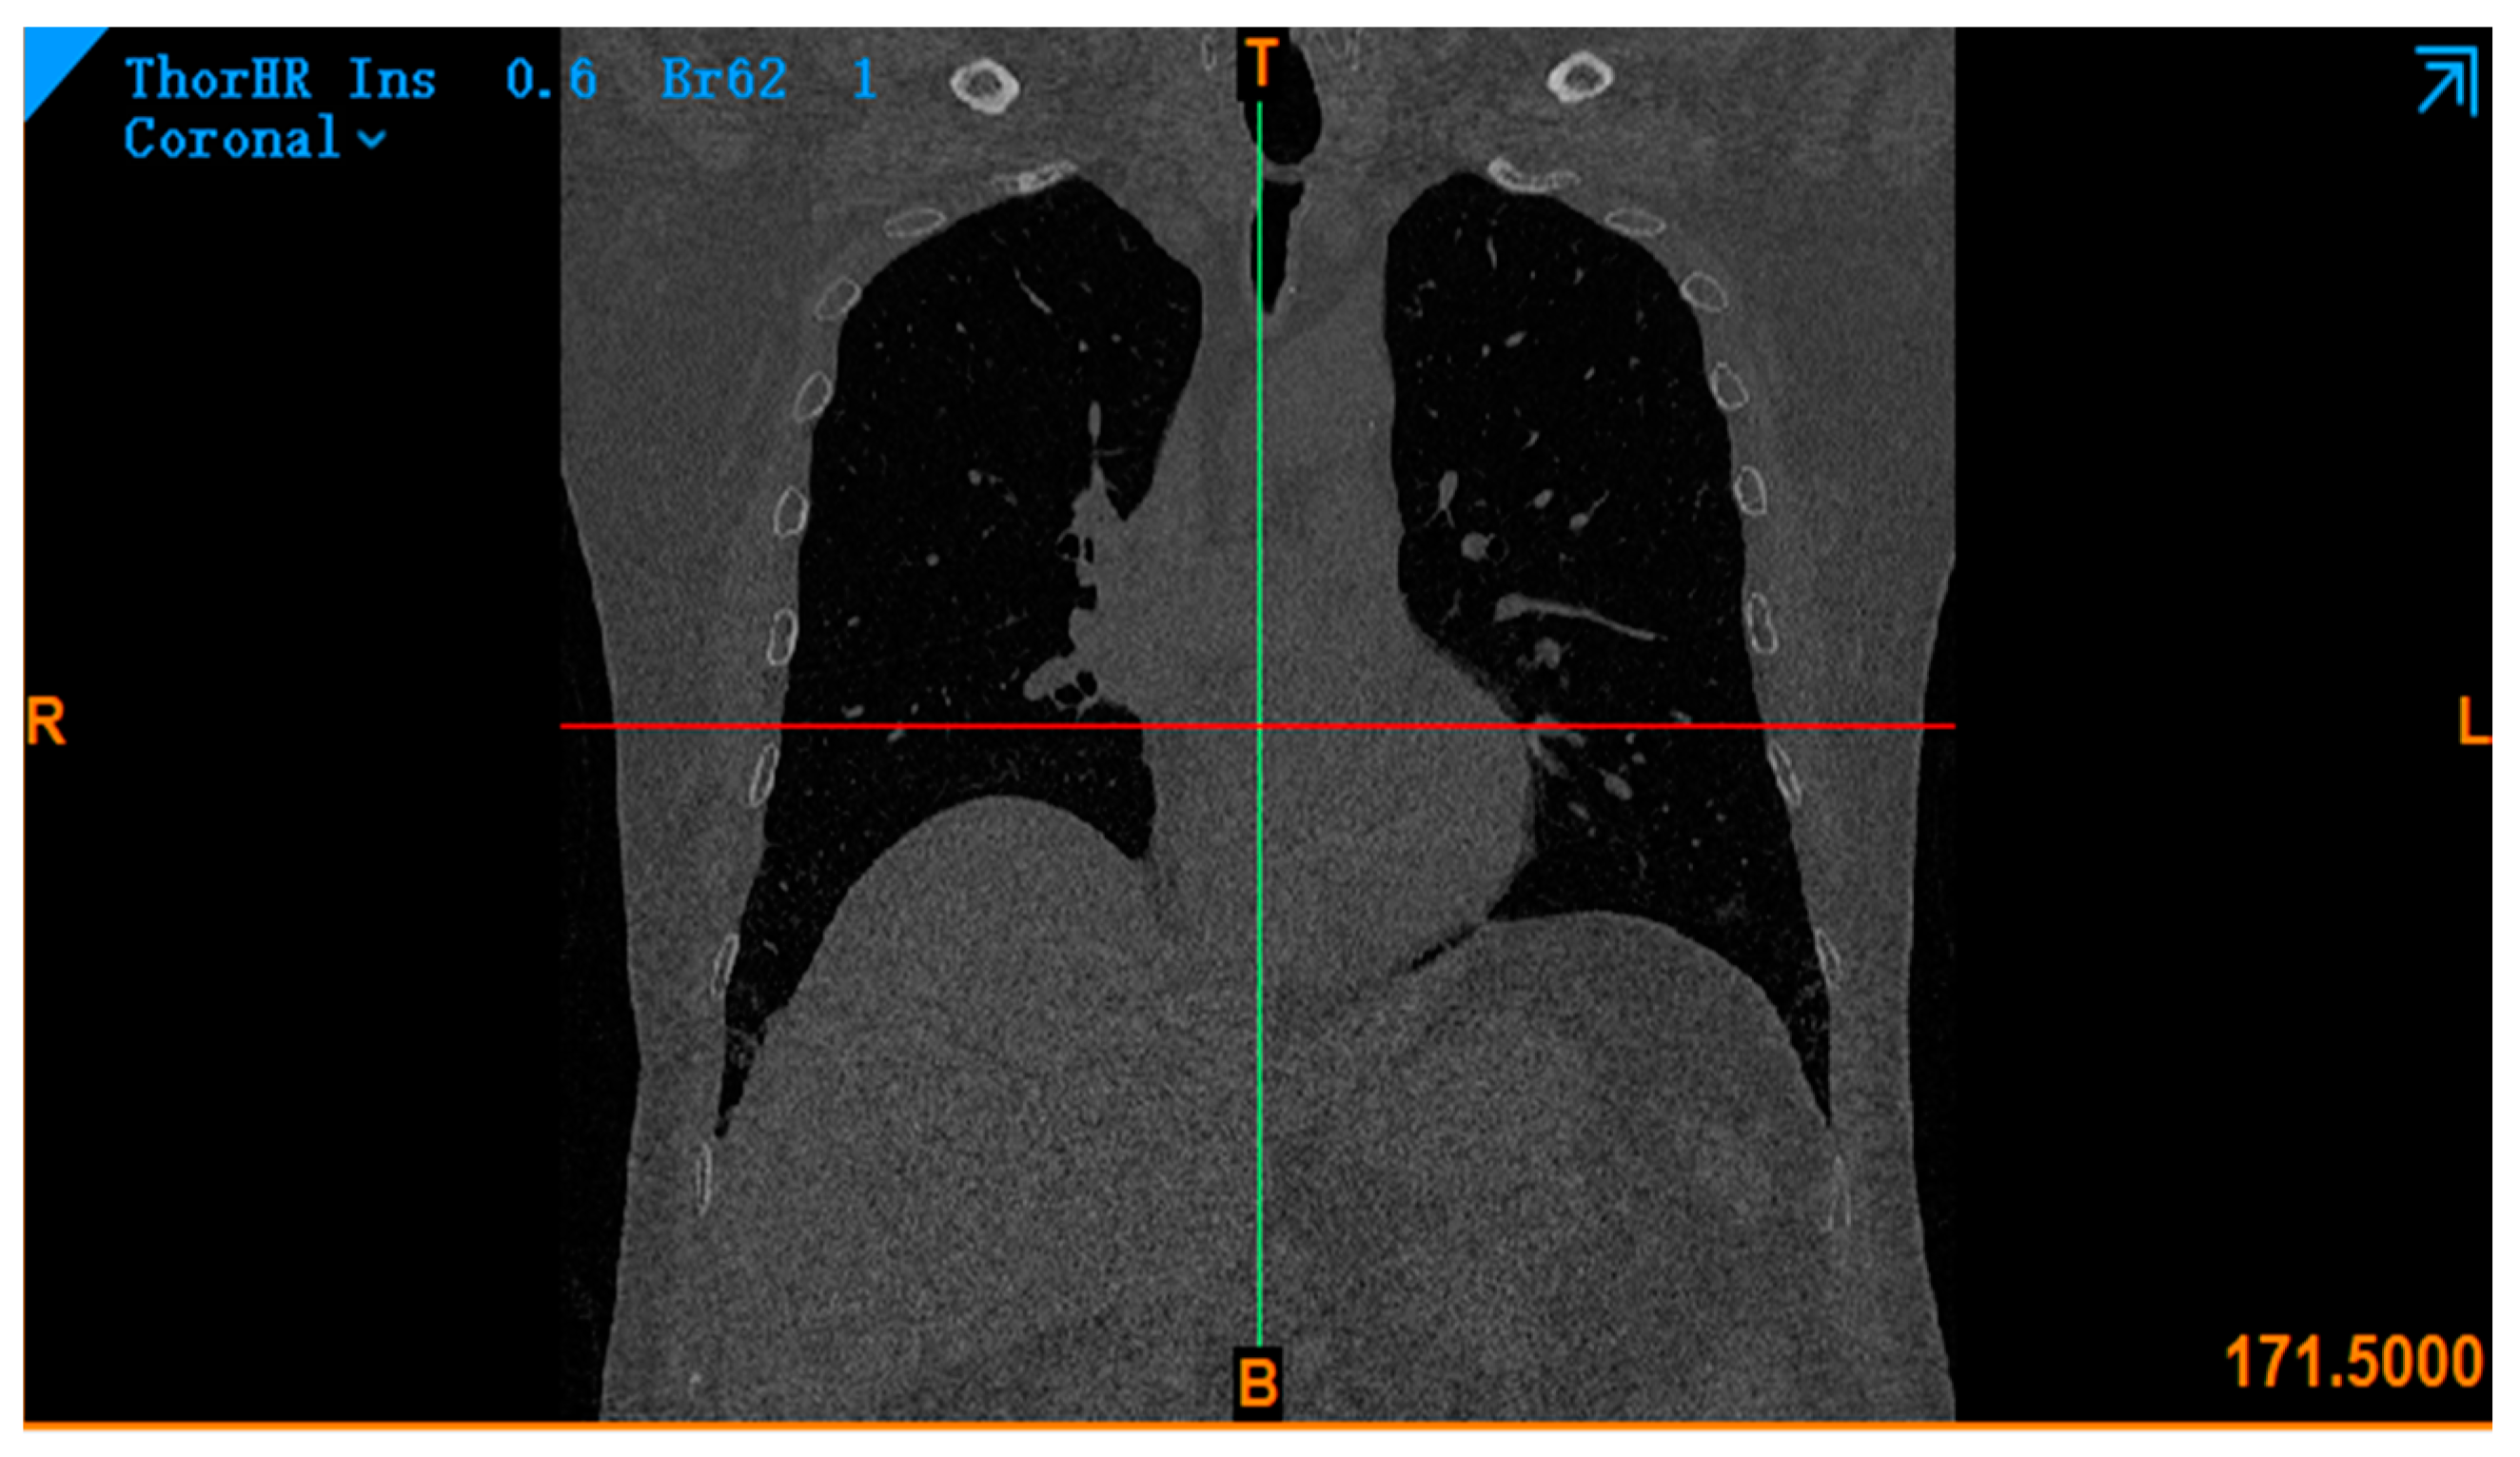

8. Simulation of COVID-19 Models